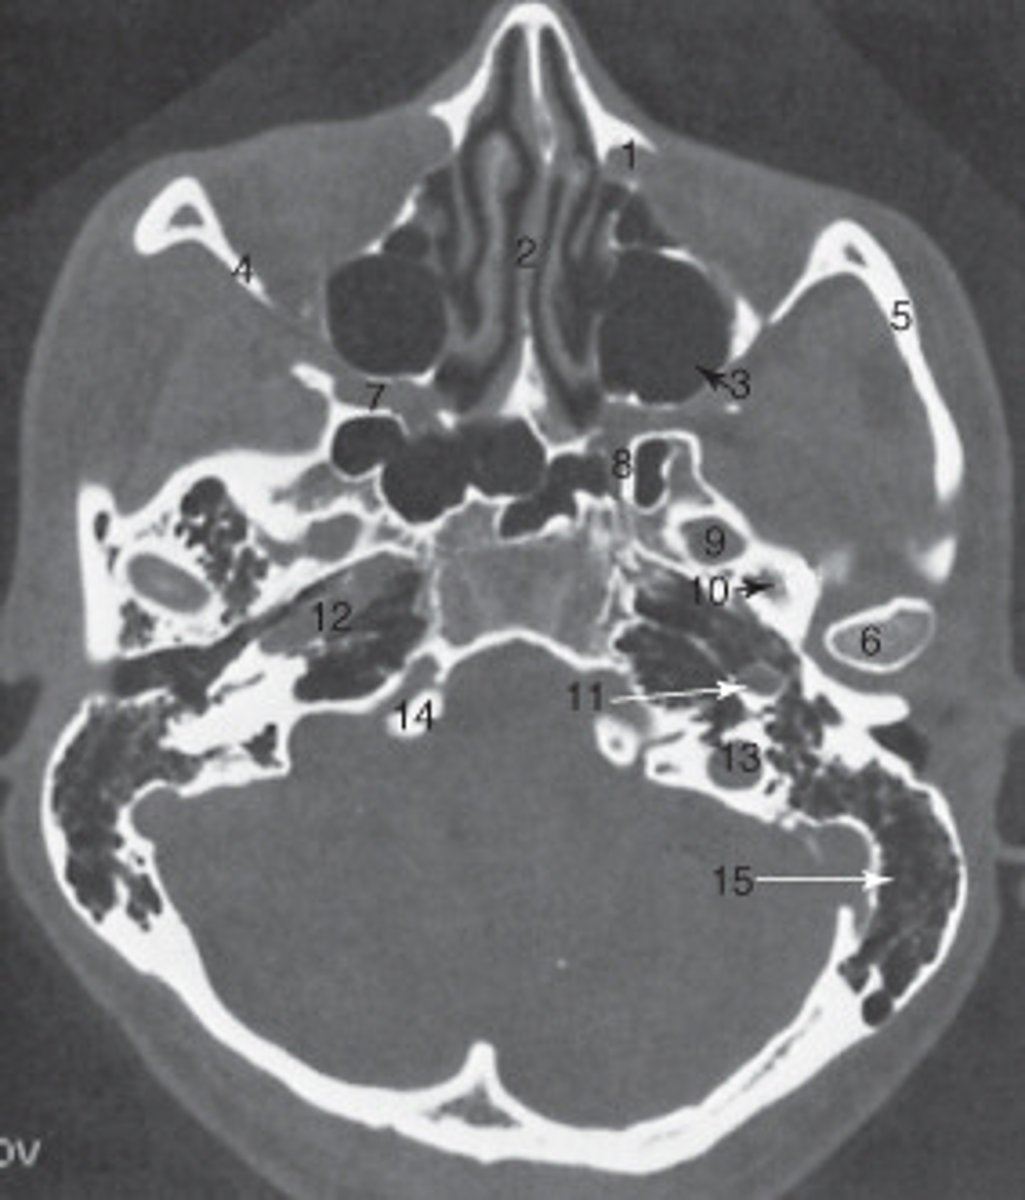

the nasal septum is labeled:

<p>the nasal septum is labeled:</p>

the mastoid air cells are labeled:

<p>the mastoid air cells are labeled:</p>

the structure labeled 6 is the:

<p>the structure labeled 6 is the:</p>

the structure labeled 5 is the:

<p>the structure labeled 5 is the:</p>

the ethmoid sinuses are labeled:

<p>the ethmoid sinuses are labeled:</p>

the zygoma is labeled:

<p>the zygoma is labeled:</p>

the lateral orbital wall is labeled:

<p>the lateral orbital wall is labeled:</p>

the structure labeled 3 is the:

<p>the structure labeled 3 is the:</p>

the structure labeled 7 is the:

<p>the structure labeled 7 is the:</p>

The sphenoid sinus is labeled:

<p>The sphenoid sinus is labeled:</p>